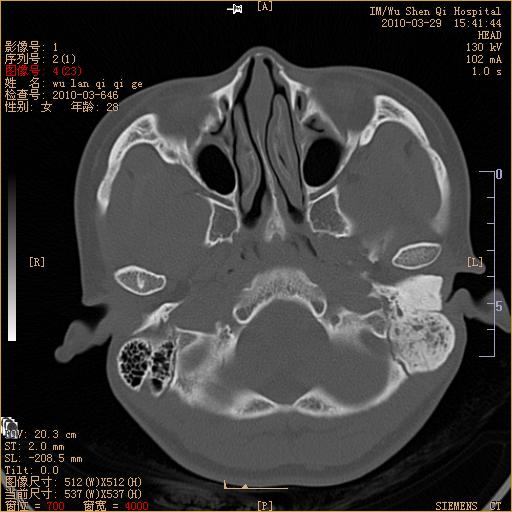

标题: CT25398:女,左耳流脓两年余,带有异物 [打印本页]

标题: CT25398:女,左耳流脓两年余,带有异物

左侧中耳乳突炎,不排除胆脂瘤形成。

左侧中耳乳突炎,胆脂瘤形成。

左侧中耳乳突炎,不排除胆脂瘤形成

1)左侧慢性中耳乳突炎并肉芽肿(或胆脂瘤)形成。2)考虑左侧颞骨慢性炎症伴骨质增生硬化,不排除骨纤。